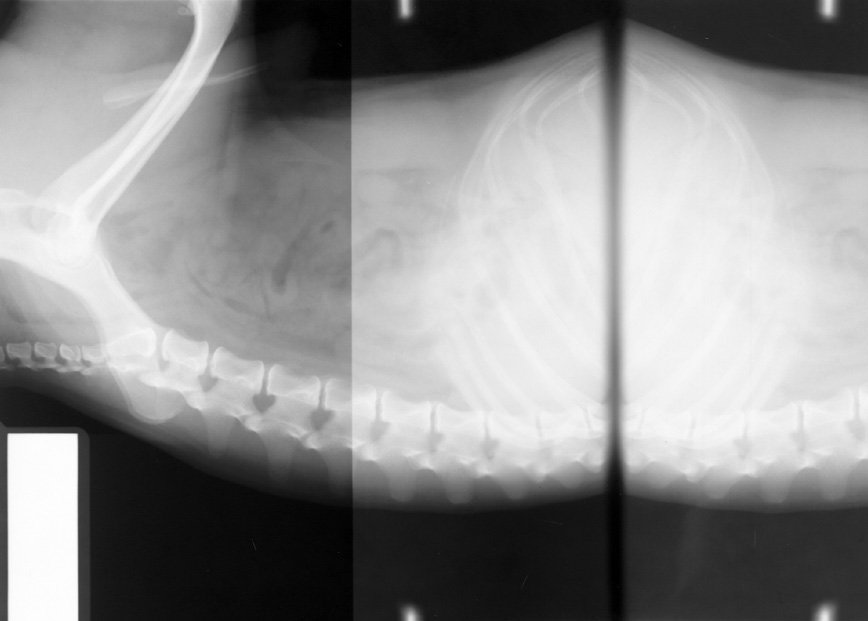

Film folded in cassette during exposure (double image